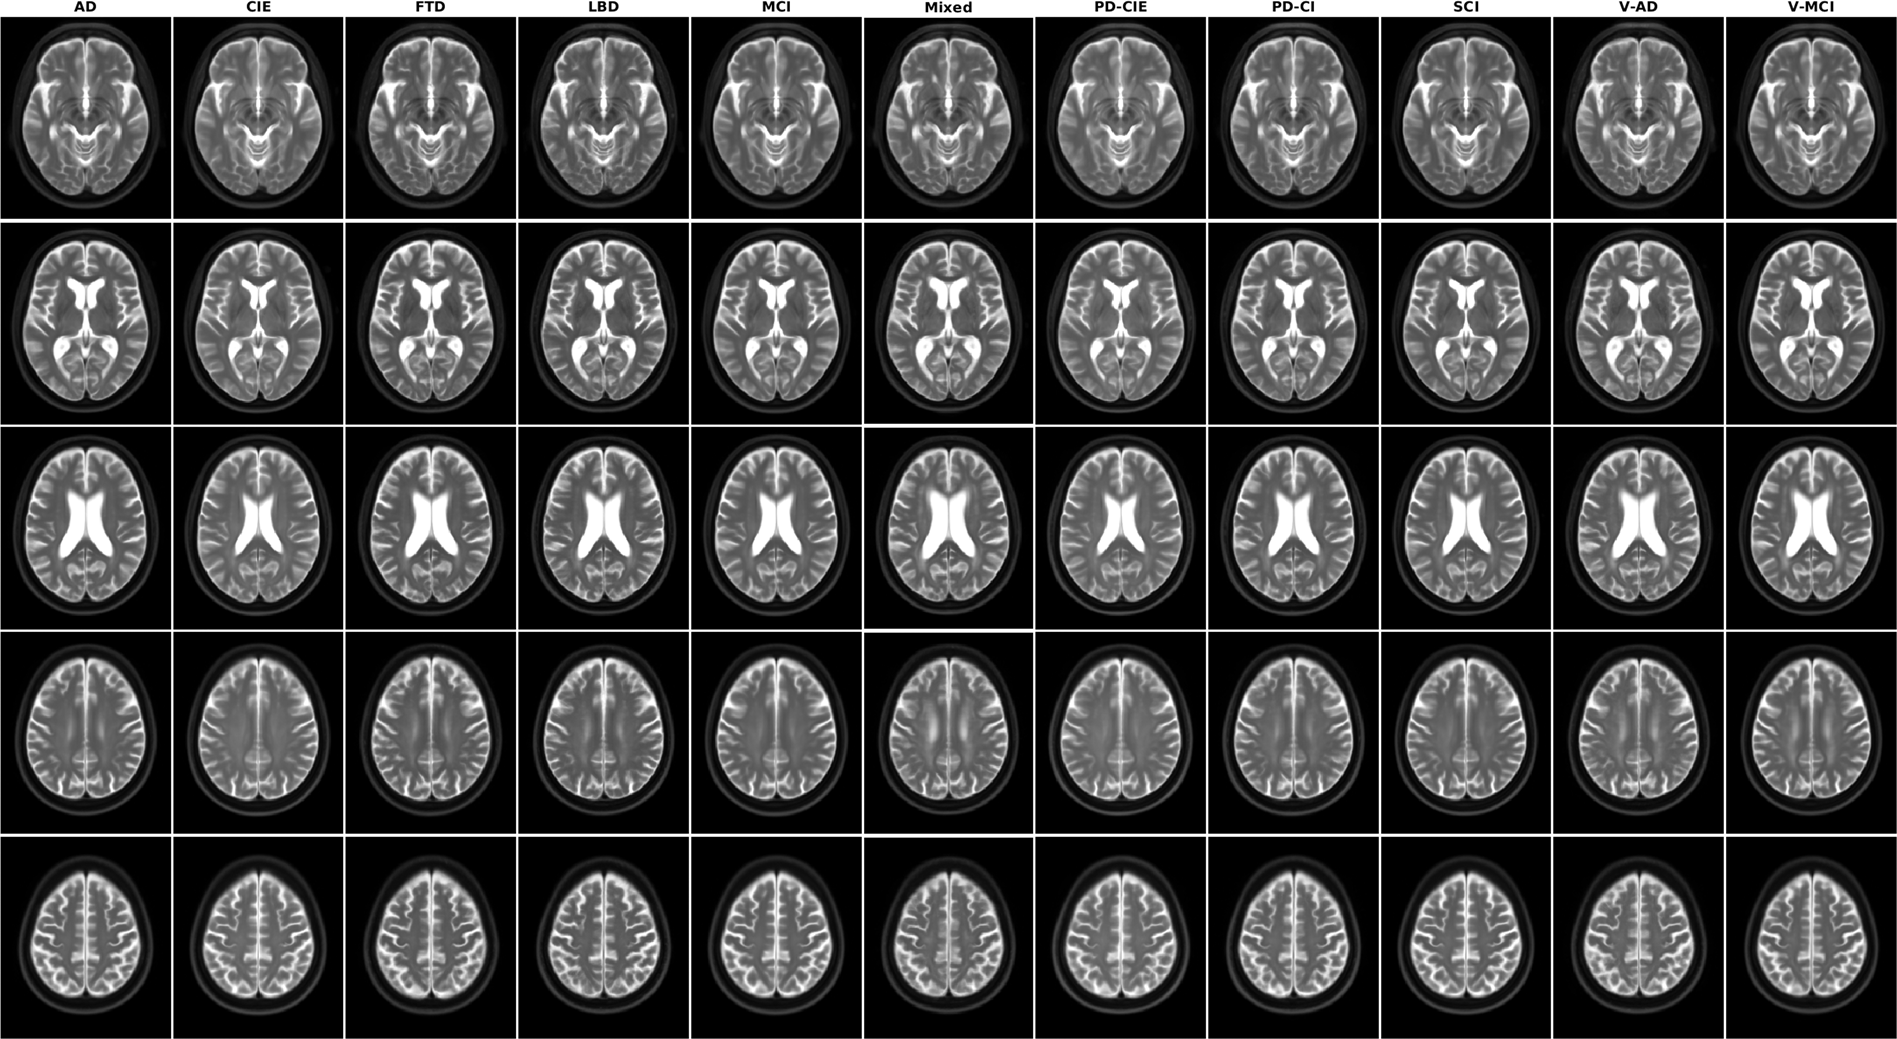

Axial slices of T2w average templates for all diagnostic groups.